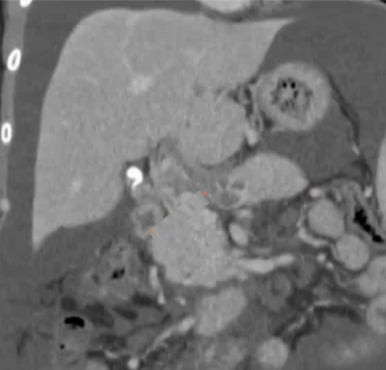

该程序包含以下步骤: 经脾脏入路:在超声引导下,刺穿脾静脉内的一个实质内分支。 在通过脾静脉造影确认了静脉通路后,导管和导丝被推进,以穿过脾静脉并抵达血栓化的门静脉。在门静脉/右门静脉分支处放置圈套器,为TIPS穿刺精准定位。TIPS穿刺圈套器,并穿过圈套器完成TIPS

步骤: 鉴于慢性血栓形成的复杂性: 一种经脾脏途径的门静脉再通术(PVR)。 随后是经颈静脉肝内门体分流术 。

结果:术后影像学检查显示门静脉和脾静脉的血流情况有所改善,且残留血栓极少。